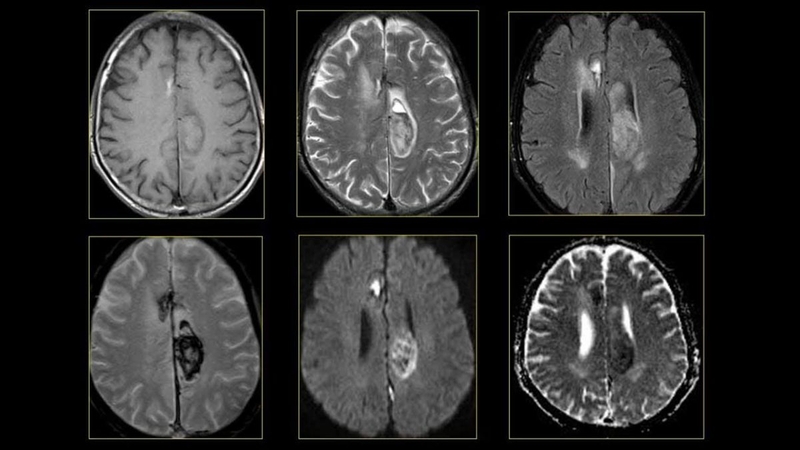

Chụp cắt lớp vi tính (CT) và chụp cộng hưởng từ (MRI) là các kỹ thuật hình ảnh giúp tạo ra hình ảnh chi tiết của não và các mạch máu. Những xét nghiệm này giúp xác định được vị trí khu vực xơ vữa hoặc vị trí có tổn thương.

CTA và MRA là các kỹ thuật chụp mạch máu tiên tiến sử dụng CT hoặc MRI để tạo ra hình ảnh chi tiết của các động mạch não, giúp xác định mức độ và vị trí của xơ vữa động mạch não.